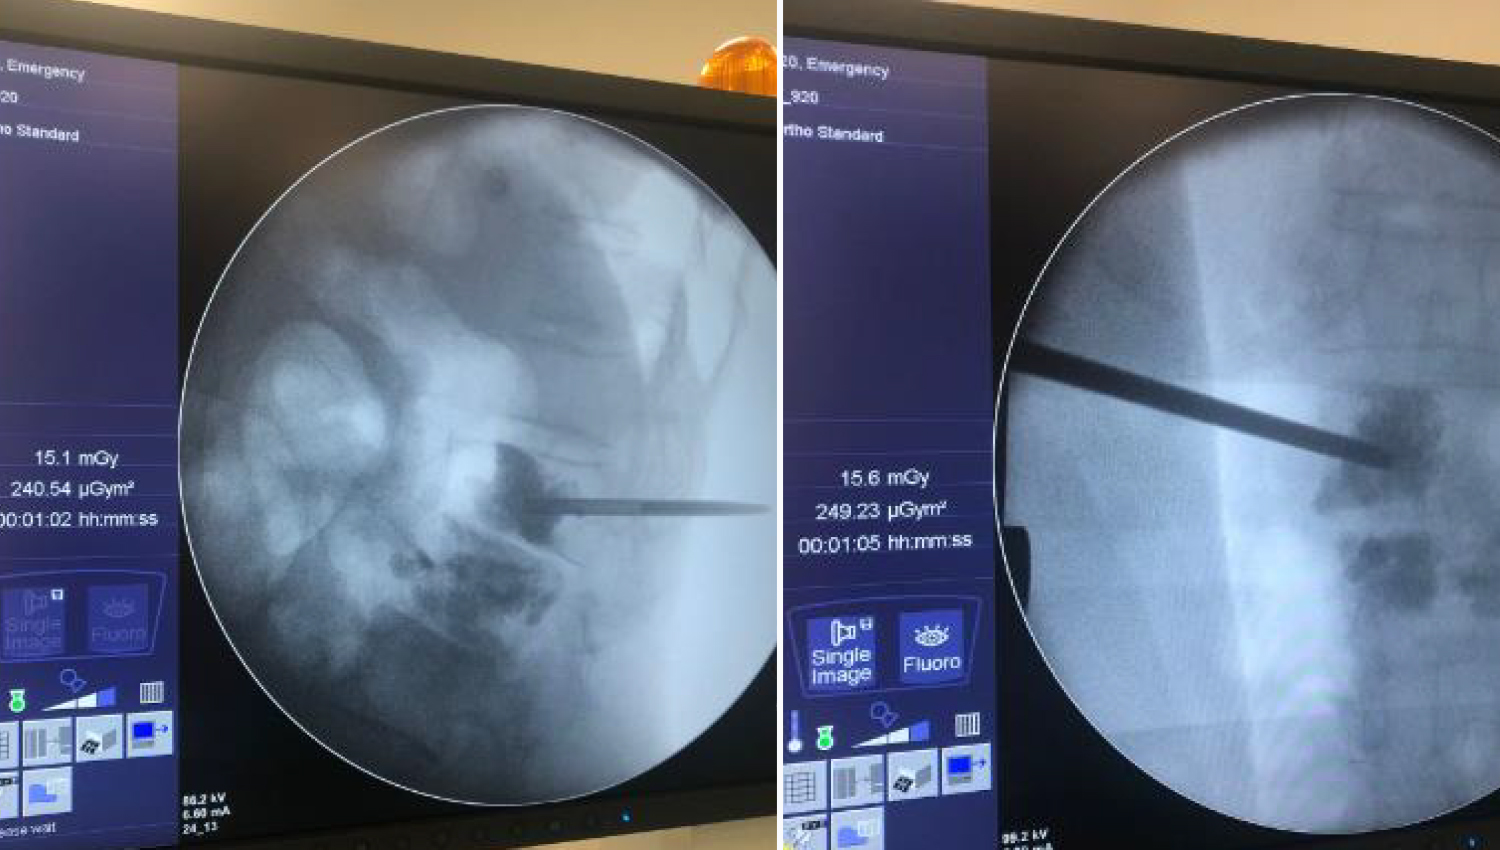

4.Bone Filler and Pusher Cannulated Screw waiting in the prepared state are prepared to be applied to the defect area. With the application of Bone Cement, the change in imaging is observed.

5.After the implantation, the patient is closed.

6.Final radiological imaging.